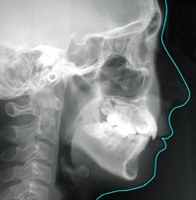

【側貌頭部X線規格写真】

【側貌頭部X線規格写真のトレース】

側貌頭部X線規格写真のトレースを用いて、上顎と下顎の骨格的なバランスや上下の前歯の歯の傾きなどを数値的に解析して、 問題点をスクリーニングをします。

側貌頭部X線規格写真のトレースから横顔を評価したり、骨の決められた点を結んで上顎と下顎、骨格的なバランスを視覚的に調べます。